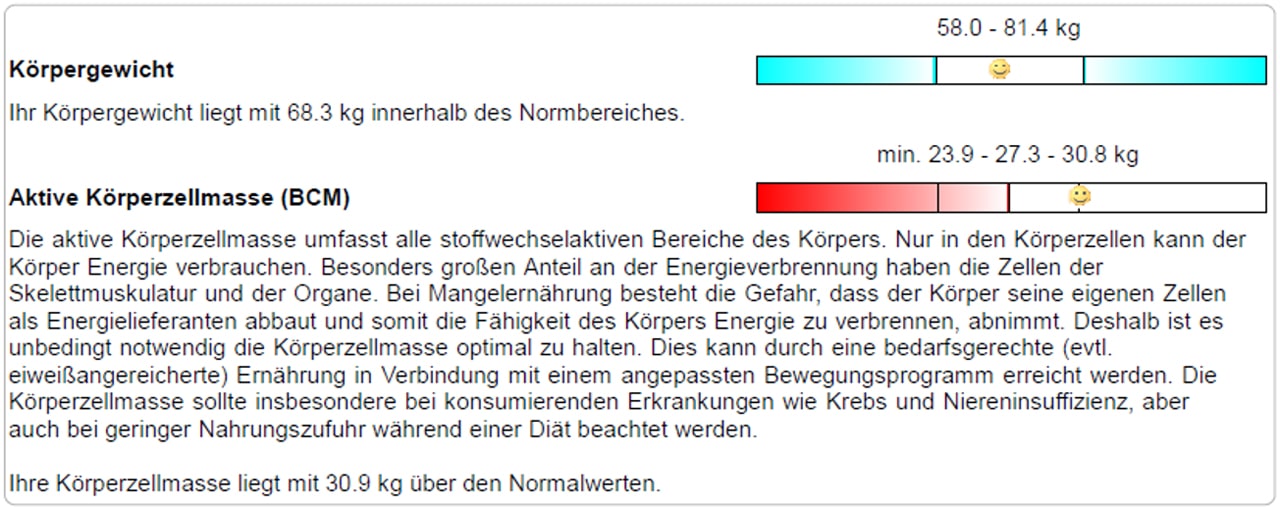

Darstellung der Auswertungs-Ergebnisse

Die Entwicklung und die Wirkungen der Trainingsmassnahmen und begleitender Ernährungsumstellungen können mittels Balkendiagramm dargestellt werden.

Dieser junge Patient macht seit Jahren Krafttraining. Man kann sehen, dass sich der Fettgehalt massiv reduziert hat, die BCM deutlich zugenommen hat und das ECW abgenommen hat.